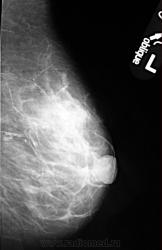

- https://radiomed.ru/sites/default/files/styles/case_slider_image/public/user/1787/P1010700.JPG?itok=Vvz4BiPA

На фоне фиброзной мастопатии определяются с обеих сторон рассеянные микрокальцинаты и мелкие стромальные, а справа в в/н квадранте подозрительные сгруппированные - нужна пункция